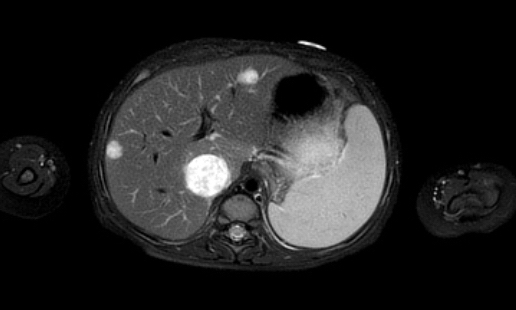

Hình ảnh

Hình ảnh MRI của một bé gái chín tháng tuổi có khối u ở bụng trái. MRI cho thấy khối u tuyến thượng thận trái, một phần đặc, một phần nang. Có nhiều di căn gan.

Khối u đã được sinh thiết. Có tình trạng chảy máu liên tục qua kim dẫn đường. Vào cuối thủ thuật, hai nút bọt gelatin đã được đặt vào (các dải tăng âm (mũi tên)).